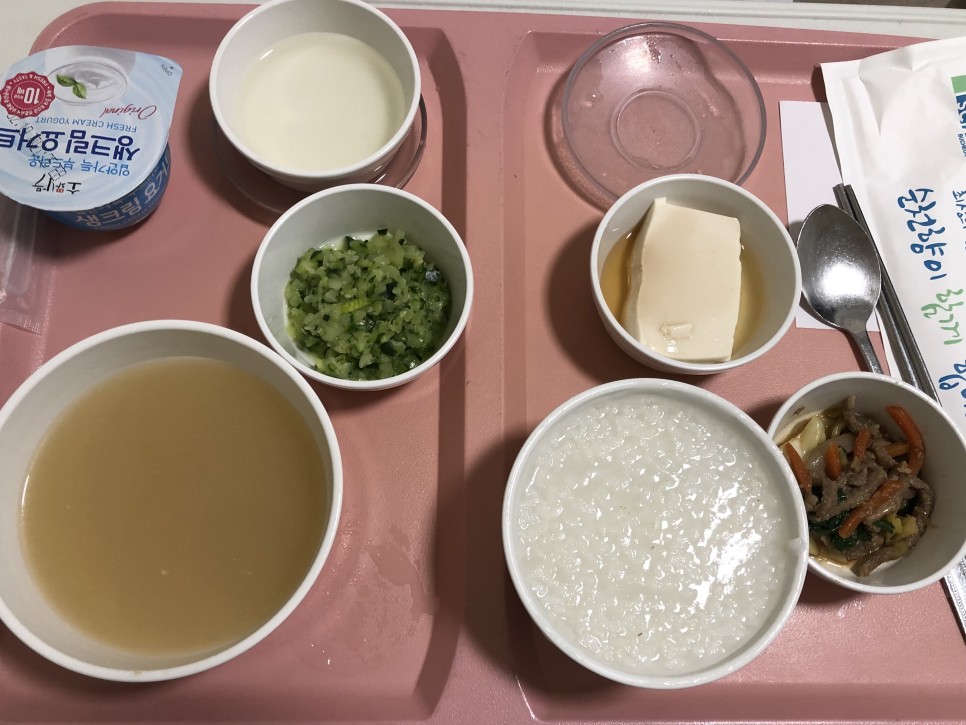

수술 1일째의 아침

아침밥인데 저 오른쪽 고기는 뭘까요? …. 절 놀리는 거예요…ㅠㅠ당연히 먹지도 못했죠

밥도 거의 못 먹고 연두부와 요구르트를 열심히 먹었습니다( ´ ; ω ; ` )